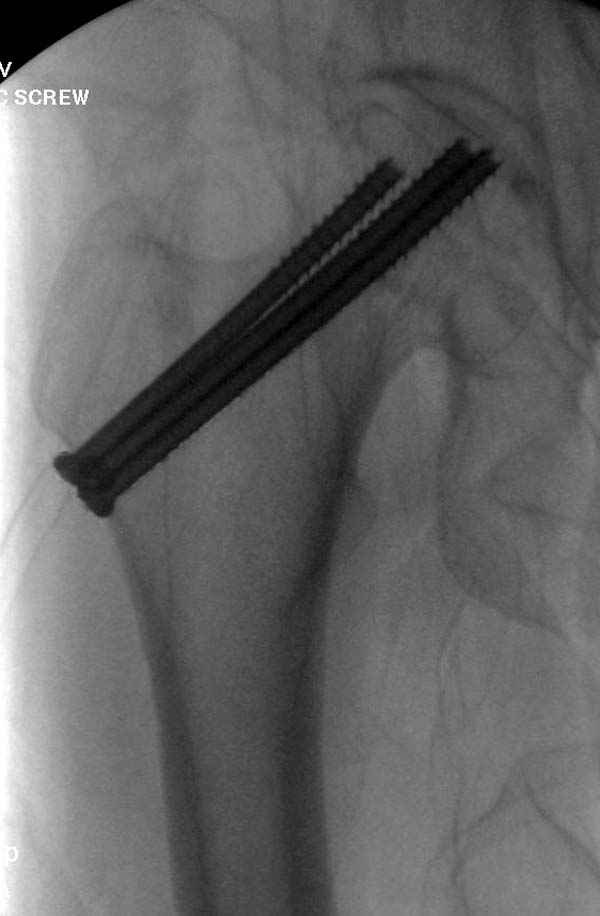

в течение первых 72 часов после перелома, остеосинтез тремя спонгиозными шурупами.

Профилактику дальнейшего раскола неполного перелома шейки провели тремя канюлированными шурупами.

Наверное речь идет насчет parallel guide из набора. Применяем по возможности всегда, но,

как видно на снимке, не всегда получается

паралельно.

Такие несмещенные переломы обычно для молодых резидентов, и бывают технические неточности, но в этом случае посчитали фиксацию адекватной.